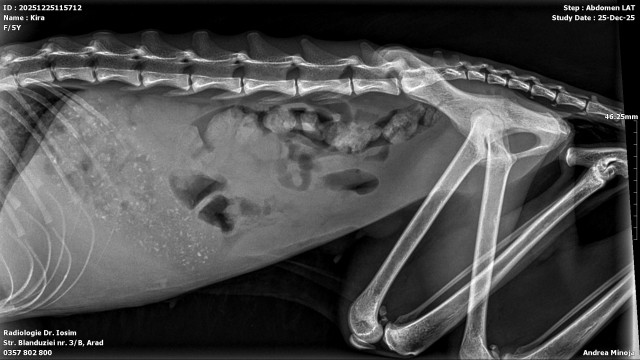

Pisica cu pancreatita

Urgenta de craciun este o pisica cu pancreatita. Am facut analize de sange si radiografii. Acum o perfuzam.